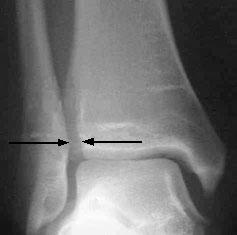

Grading of sprains. (A) The grade I sprain is characterized by stretching of the anterior talofibular and calcaneofibular ligaments. (B) In the grade II sprain, the anterior talofibular ligament tears partially, and the calcaneofibular ligament stretches. (C) The grade III sprain is characterized by rupture of the anterior talofibular and calcaneofibular ligaments, with partial tearing of the posterior talofibular and tibiofibular ligaments.临床上常用一系列体格检查(for example, inspection, palpation, weight-bearing status, special tests) 判断踝关节的受损情况。特殊之处在于,我们往往需要触诊胫骨和腓骨的全长,以判断是否有骨折情况,若腓骨近端出现骨折,则为Maisonneuve fracture,临床漏诊率较高,这点我们在后文还会提及。触诊踝关节察觉痛感或流动感则怀疑 距骨圆顶骨软骨损伤(osteochondral talar dome lesion) ,这种损伤往往不会立刻在影像学检查中显现,而是在二至四周后出现相关表现。沿第五跖骨基部触及的柔软感往往提示 腓骨短肌腱(peroneal brevis tendon) 的撕裂。除此之外,还有一些特殊检查用以判断受损。其一是 anterior drawer test ,通常用来判断腓前韧带的完整度;另一是 inversion stress test ,通常用来判断跟腓韧带的完整度。

MRI检查一般显示出胫腓之间出现一大于6mm的间隙,少数情况可见胫腓下联合完全分离(如图)。